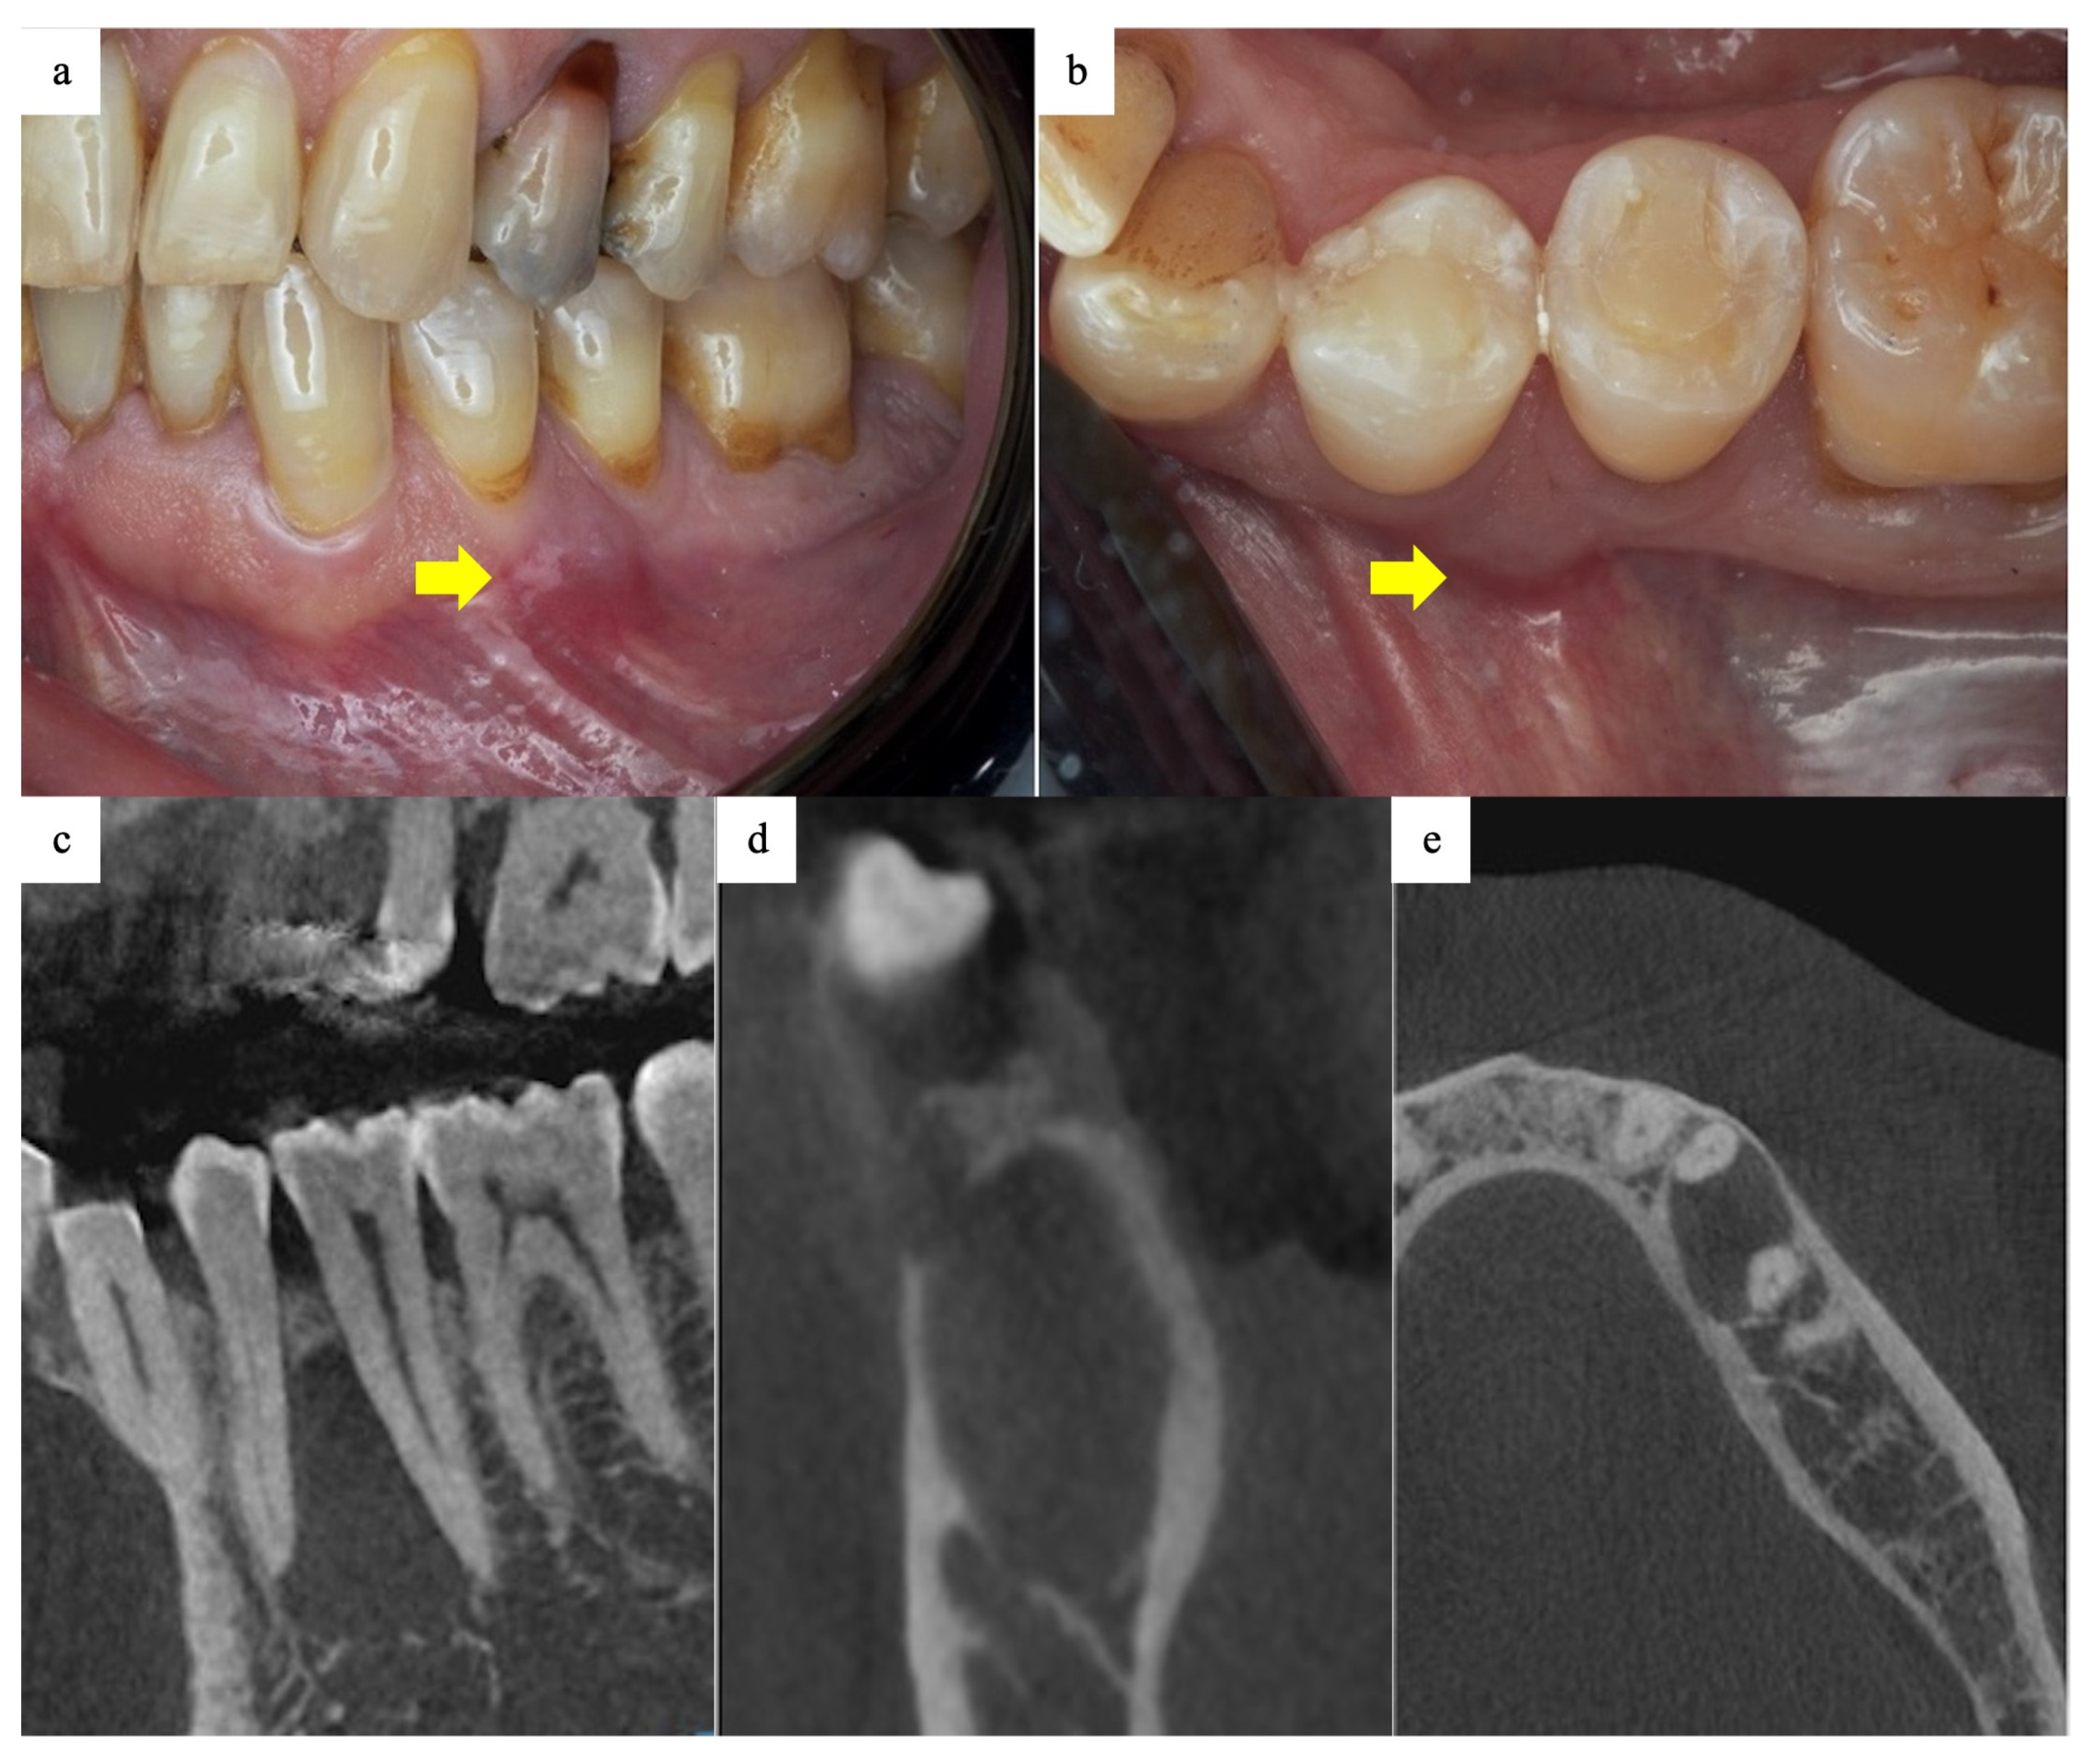

2.1. History and Examination

2.5. Follow-Up and Outcomes